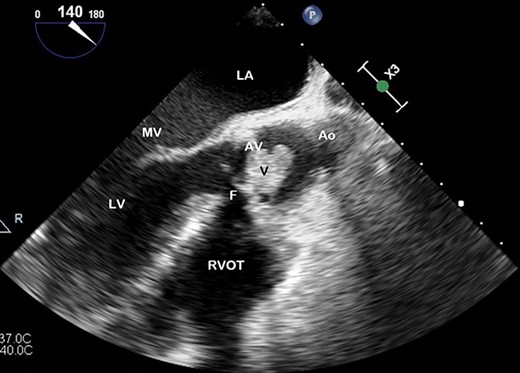

TOE, long axis demonstrating a vegetation (V) on the AV obstructing the left ventricular outflow tract; Ao, aorta; F, fistula; LV, left ventricle; MV, mitral valve.

The patient developed complete heart block, and subsequently, Torsades de Pointe, requiring an isoprenaline infusion, pacing via a temporary venous pacing system (and removed post-operatively) and urgent coiling of a large 4.8 × 2.5 cm right middle cerebral artery mycotic aneurysm 1 day prior to his redo-valve surgery. A repeat TOE demonstrated severe aortic regurgitation, prosthetic valve abscess, dehiscing and fistulizing from the aortic root to right ventricle (RV) on colour-flow doppler (Fig. 3). Proceeding to surgery, on inspection of the aortic root—findings confirmed a largely destroyed AV, multiple valvular vegetations and fistulization from the aortic root just below his right coronary cusp to his RV. A redo-sternotomy was performed, central cannulation was utilized—cross-clamp and bypass times were 89 and 141 minutes, respectively. Abscess debridement and an AVR (#23 Carpentier-Edwards Perimount magna-ease) were undertaken, with the fistula closed with the valve sutures, and a post-operative TOE confirmed no persisting fistula or peri or para-valvular leak around the new AV prosthesis, indicating significant improvement. He was referred for counselling with the Drug and Alcohol Service during his admission with extensive planned follow-up to maintain abstinence from IV drug use. The patient remained in sinus rhythm, completed 6 weeks of antimicrobial therapy and discharged home with no issues on follow-up.

Preoperative TOE, long axis with colour flow highlighting the vegetation (V) obstructing flow through the AV and the fistula (F) which has developed from left ventricular outflow tract to RVOT.